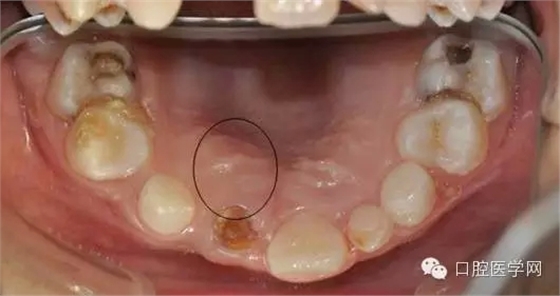

俺一般不喜歡浪費(fèi)國家資源,能拍小牙片的堅(jiān)決不拍CBCT.這個(gè)病例還真不敢輕易下刀。兩顆埋伏一二擠在一起,位置較深。讓步了,拍CT吧。

CBCT后影像

我們能夠更好的了解牙齒的立體空間結(jié)構(gòu).好東西哈,清晰。